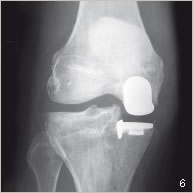

La prothèse comportant une pièce fémorale et une pièce tibiale est alors implantée de manière à assurer une stabilité parfaite du genou et une mobilité la plus complète possible (figures 4 et 6). Son bon positionnement peut être contrôlé par l’assistance informatique.